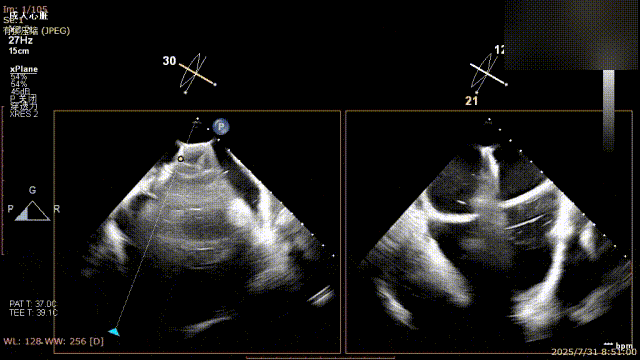

手术过程中,麻醉与围术期医学科副主任医师马金本确保麻醉过程平稳。心脏大血管外科主治医师董明亮穿刺股静脉置入血管鞘,并在心脏超声科梁皓主任及段福建教授TEE引导下,顺利穿刺房间隔,房间隔穿刺高度4.9cm。随后,在王安彪主任以及刘洋教授指导、心脏超声科梁皓主任TEE引导下,董明亮医师沿输送系统将延展呈“一字型”状态的国产夹合器送至左房,缓慢关闭夹合器并进行弹道测试。调整夹合器位置和方向后,董明亮医师再次将夹合器延展呈“一字型”完成跨瓣,避免发生腱索缠绕,成功捕获瓣叶后关闭夹合器,二尖瓣反流显著下降。夹合器完全解离后,超声示二尖瓣反流程度显著下降,残余反流0,平均跨瓣压差1mmHg,手术圆满成功。

解离后瓣叶及反流